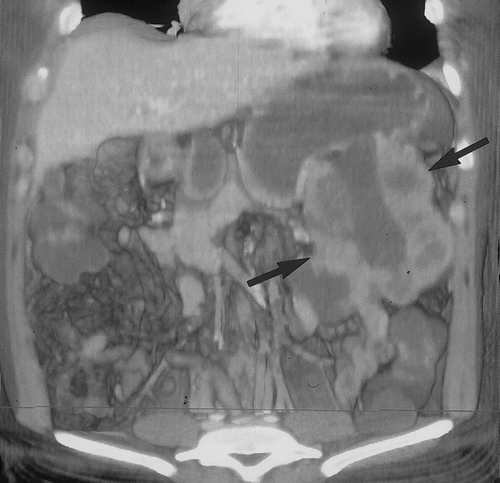

Gastric Varices

Gastric varices can occur in association with esophageal varices in patients with cirrhosis and portal hypertension. In these patients there is increased resistance to portal flow into the liver. Therefore, blood must find and alternative pathway to the heart, which includes the perigastric and periesophageal vessels. Isolated gastric varices, without esophageal varices can also occur in patients with splenic vein thrombosis or occlusion. This is typically seen in patients with pancreatitis and splenic vein thrombosis or in patients with pancreatic cancer with invasion and occlusion of the splenic vein (Figure 18) .

CT is valuable for detection of gastric varices and for identification of the underlying cause33. Gastric varices appear as enhancing tubular vessels , located primarily along the body and fundus of the stomach (Figure 18). Because they are veins, they will opacify during the portal venous phase of enhancement, and typically will not enhance on early, arterial phase studies. Collateral vessels are also commonly seen along the gastrohepatic ligament and along the course of the left gastric vein10. Gastric varices can be mistaken for gastric wall thickening, gastric cancer or perigastric adenopathy, if IV contrast is not administered. In patients with cirrhosis and portal hypertension, esophageal varices will also be present.

CT angiography is useful for detection of gastric varices. In a study by Matsumoto et al of 30 patients with gastric varices, demonstrated close agreement between the findings on 3D CT and conventional angiography34. In fact in four patients posterior gastric veins or short gastric veins were identified on 3D CT and not at conventional angiography. In this study, 3D CT studies were also used to evaluated patients after balloon occlusion of the varices34. The unlimited imaging planes possible with 3D CT imaging is definitely an advantage in trying to identify the small perigastric vessels. In addition to detection of gastric varices, CT angiography can routinely identify the arteries and veins which supply the stomach as well as anatomic varians34, 35 (Figures 19& 20).